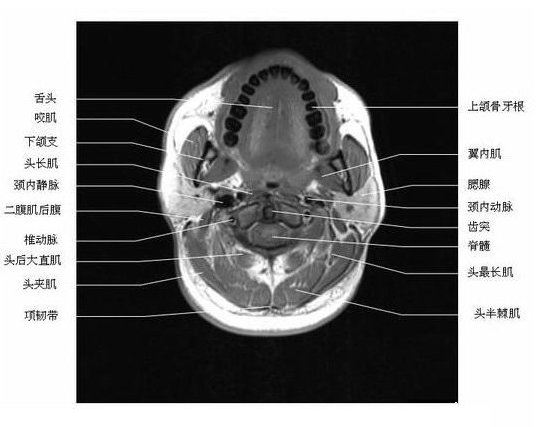

头颈部横断面-MRI

头颈部横断面